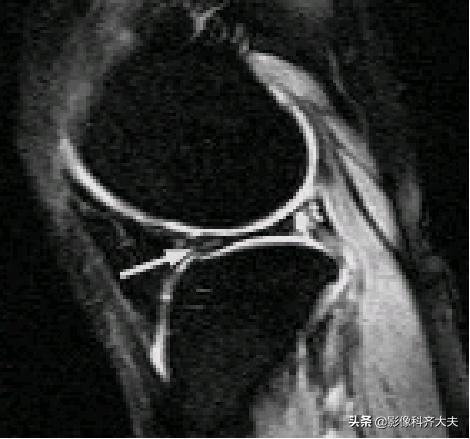

膝横韧带: